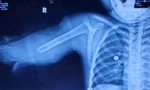

| Bàn tay phải của bà L. bị đứt rời trước khi vào phòng phẫu thuật |

Bà L. được đưa tới Bệnh viện đa khoa tỉnh Thanh Hoá trong tình trạng sốc mất máu, ý thức hoảng loạn, bàn tay phải đứt xương khối xương cổ tay phải, đứt mạch máu trụ quay, đứt thần kinh giữa, đứt thần kinh trụ, đứt gân gấp ngón 2,3,4,5 bàn tay phải và có bệnh nền đái tháo đường type 2 kèm theo.